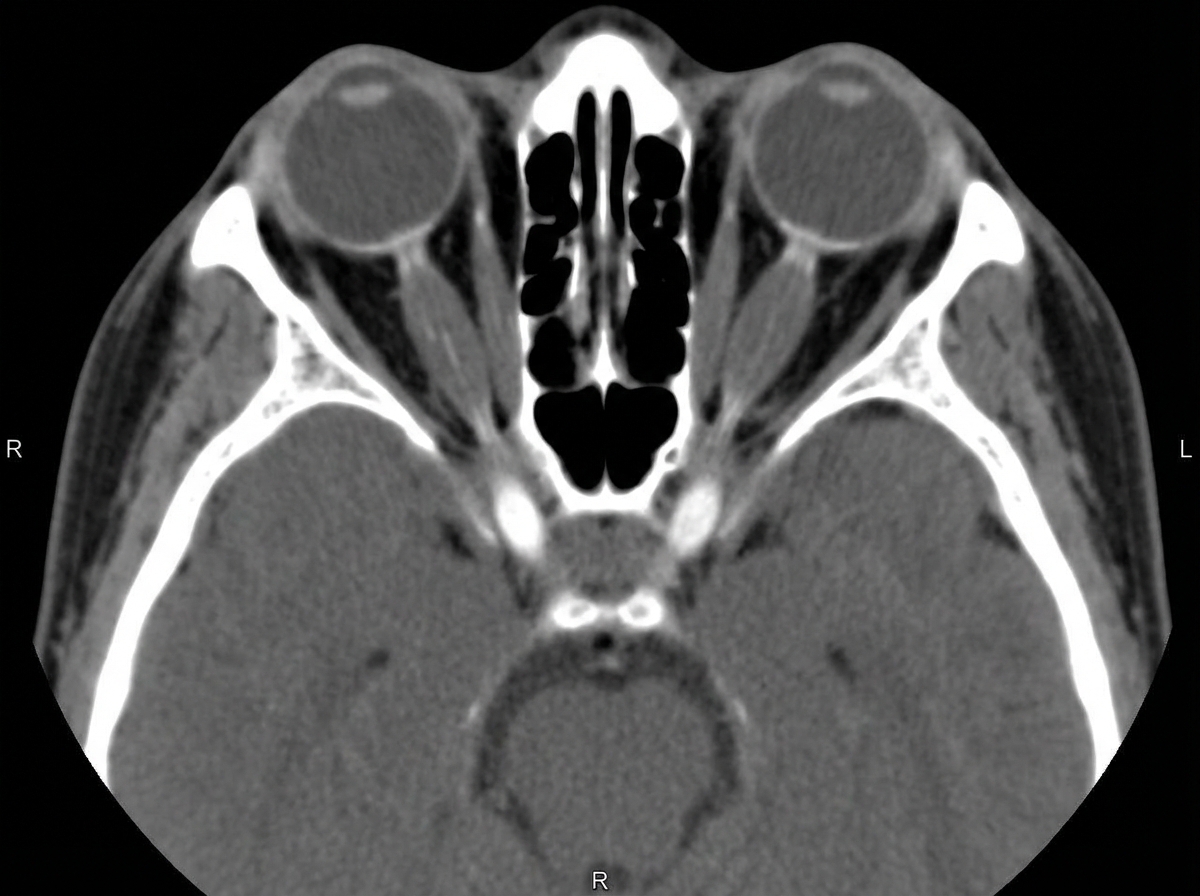

What is the cause for enlargement of the extraocular muscles shown in this CT-scan?

Explanation: ***Graves' ophthalmopathy*** - Causes **bilateral extraocular muscle belly enlargement** with characteristic **tendon sparing** on CT scan, which is pathognomonic for thyroid-associated orbitopathy. - Results from **glycosaminoglycan deposition** and **inflammatory infiltration** in extraocular muscles, commonly affecting **inferior** and **medial rectus** muscles first. *Pseudotumor* - Shows **irregular, asymmetric** soft tissue enhancement that typically involves the **entire muscle-tendon complex** without sparing tendons. - Presents as **unilateral orbital inflammation** with pain, proptosis, and **rapid onset** of symptoms over days to weeks. *Myositis* - Characterized by **muscle belly and tendon involvement** together, unlike the tendon-sparing pattern seen in Graves' ophthalmopathy. - Usually presents with **acute onset pain**, **restricted eye movement**, and **unilateral involvement** in most cases. *Rhabdomyosarcoma* - Appears as an **irregular, heterogeneous mass** with **destructive changes** and potential **bone erosion** on CT imaging. - Most commonly occurs in **pediatric patients** and presents as a **rapidly growing orbital mass** with proptosis and visual disturbances.